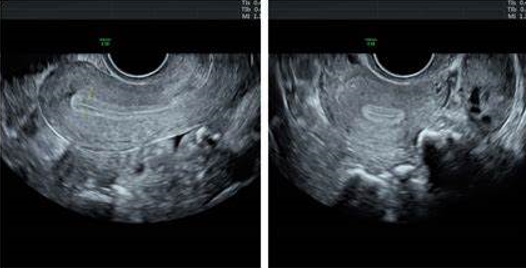

Echographie pelvienne

Se fait entre le 2é et le 4é jour du cycle

Permet l’étude de l’utérus, des ovaires

Permet le compte des follicules antraux (CFA) entre 2 et 9mm : 6 à 10 par ovaire

Recherche  des kystes ou une anomalie tubaire (Hydrosalpinx) ou une endométriose